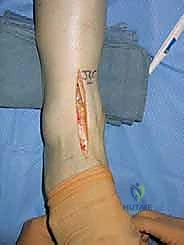

3. الشق الجراحي والوصول للمفصل

يقوم الدكتور هطيف بعمل شق جراحي أمامي (Anterior Approach) بعناية فائقة لتجنب الأوتار والأعصاب والأوعية الدموية الرئيسية. باستخدام تقنيات الجراحة المجهرية، يتم إبعاد الأنسجة الرخوة بلطف للوصول إلى المفصل التالف.

6. الإغلاق والتضميد

بعد التأكد من نجاح الزراعة، يتم غسل الجرح جيداً، وتُخاط الأنسجة والجلد بطريقة تجميلية دقيقة لتقليل الندبات. يتم وضع الكاحل في جبيرة أو حذاء طبي داعم لحمايته أثناء فترة الشفاء الأولى.